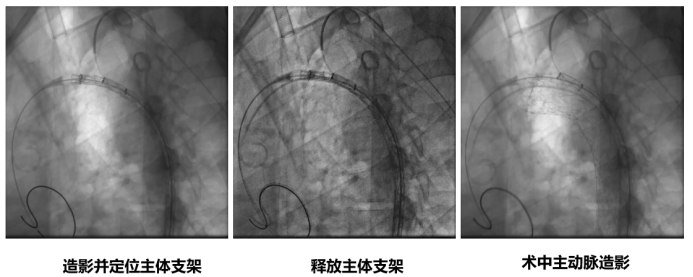

★ 病例3

27岁男性,急性主动脉夹层,破口紧邻左锁骨下动脉。

手术亮点:

TBE支架采用“导丝直出”设计,释放后无需解缠绕,操作简便;

支架柔顺性好,即使成角90°–180°也不打折;

顺应弓部运动,长期通畅率良好,五年随访结果优异。